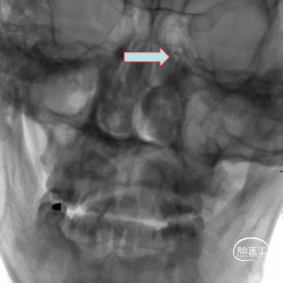

头CT(急诊):左侧小脑半球、左侧放射冠、半卵圆中心、额顶枕叶脑梗死。

头颈CTA :左侧颈内动脉末端及基底动脉重度狭窄或闭塞。

术前CT,ASPECT 8分。

术前CTA检查。